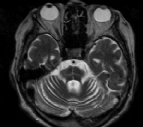

Nosso portal destina-se a estudar as imagens radiológicas em Pneumologia, mas, nesta data em que se comemora a Páscoa, não poderíamos deixar passar em branco este interessante sinal radiológico em neurologia que lembra um coelho. Hiperde...